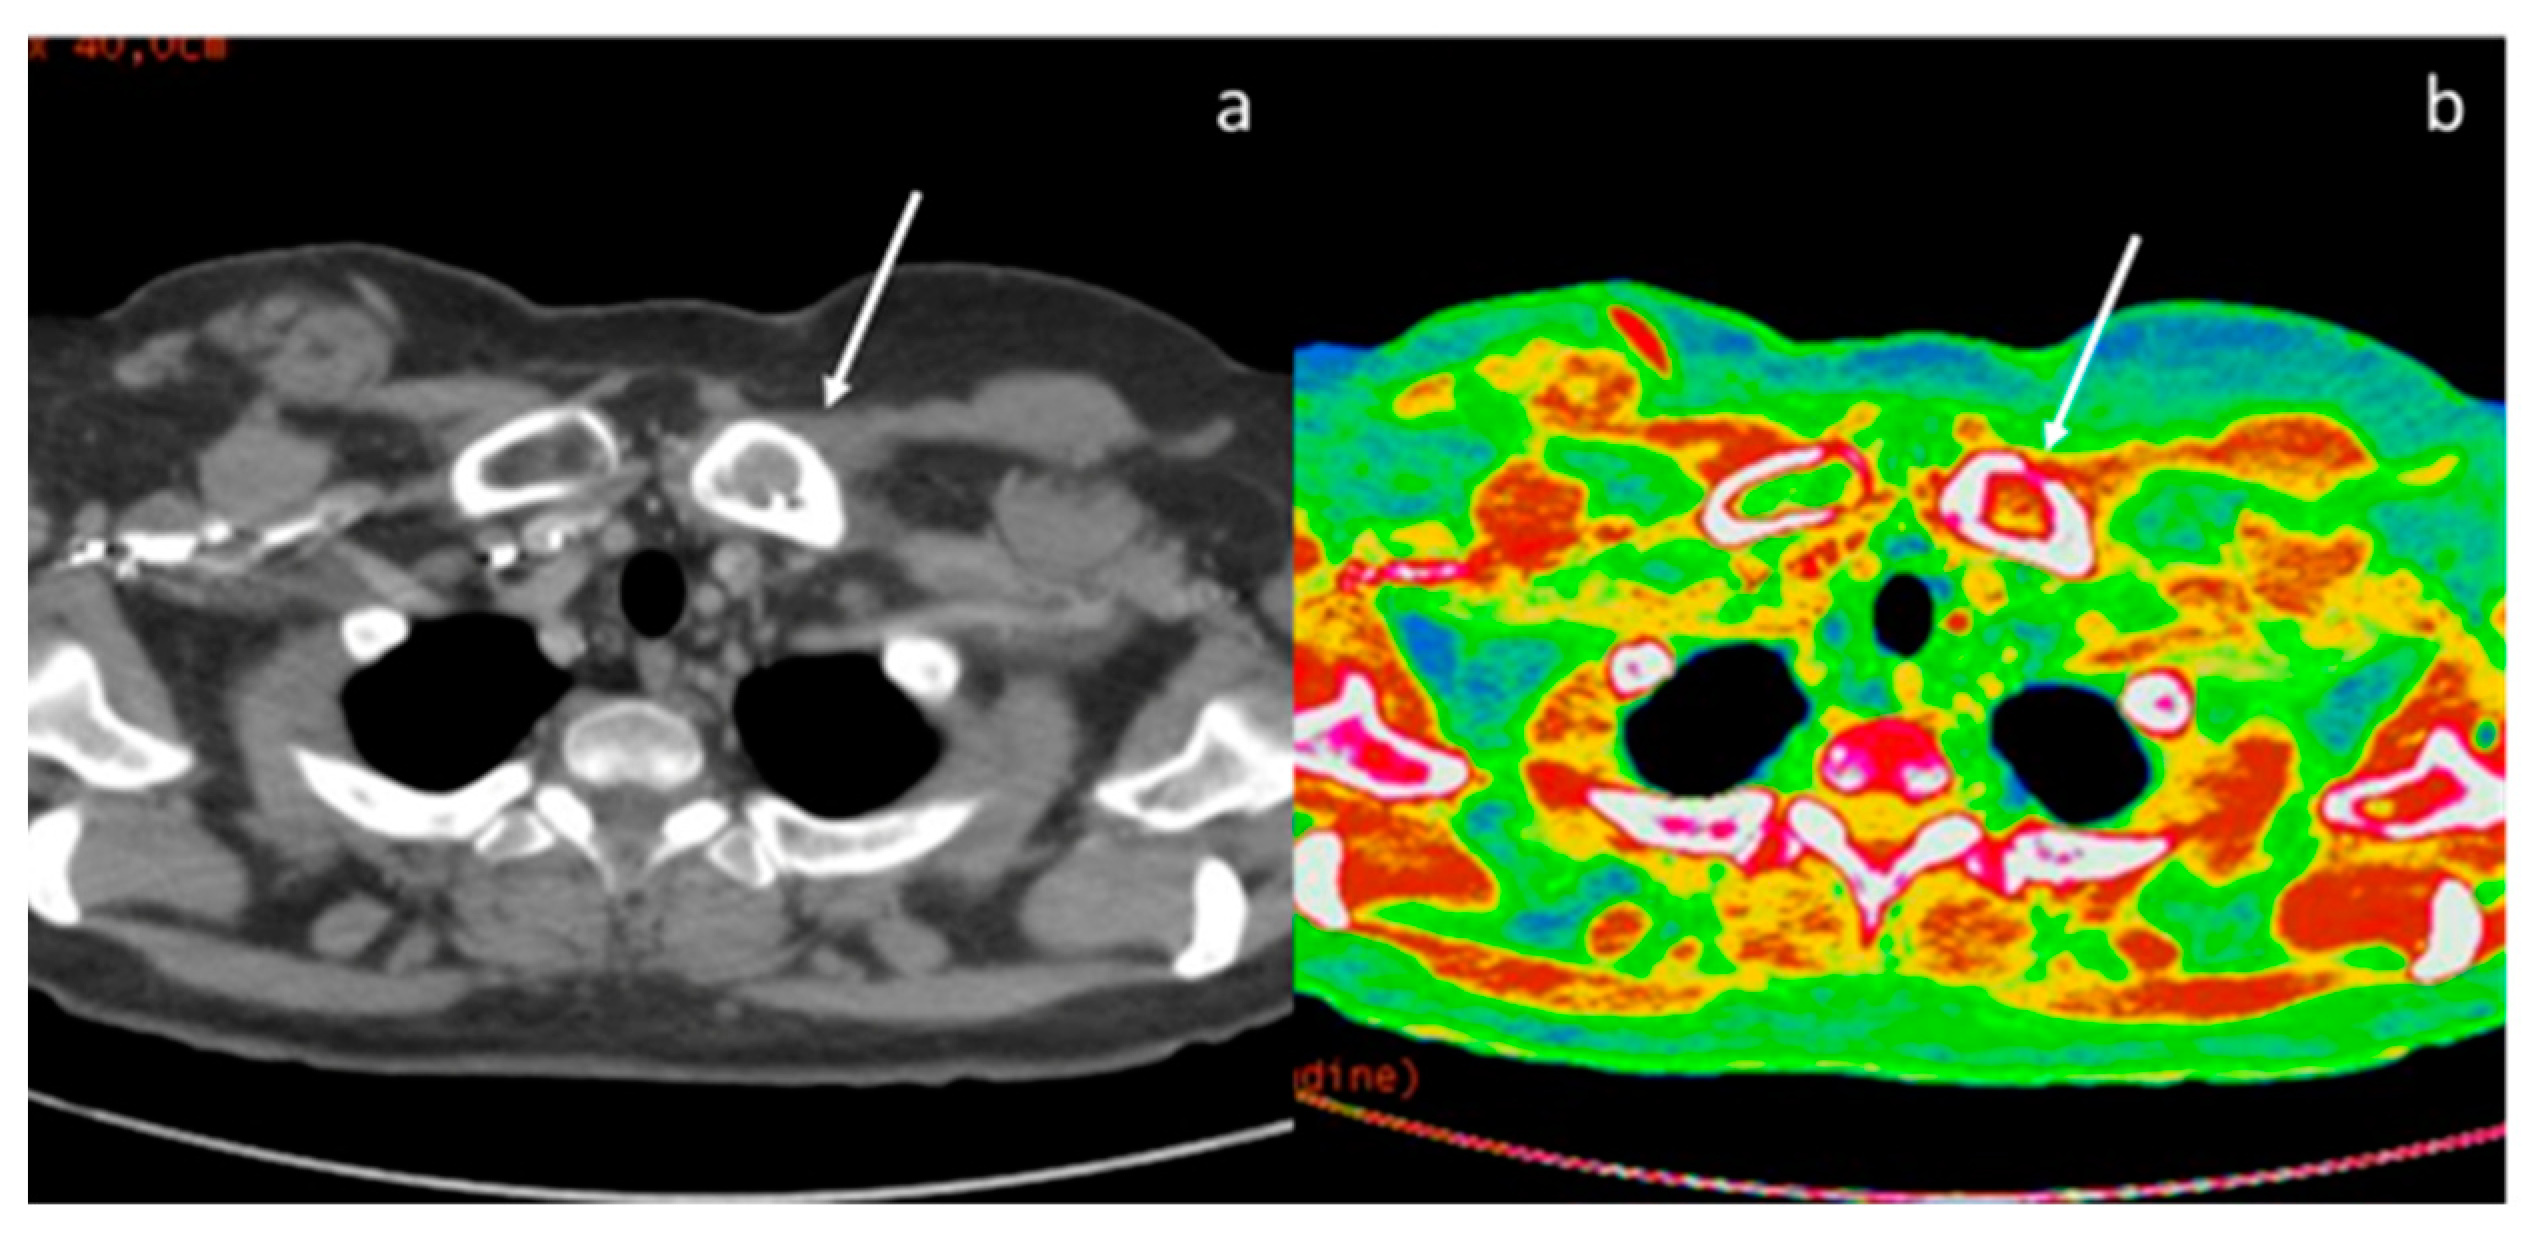

- Zhang, X.; Zheng, C.; Yang, Z.; Cheng, Z.; Deng, H.; Chen, M.; Duan, X.; Mao, J.; Shen, J. Axillary Sentinel Lymph Nodes in Breast Cancer: Quantitative Evaluation at Dual-Energy CT. Radiology 2018, 289, 337–346. [Google Scholar] [CrossRef] [PubMed]

| Zhang et al. [60] Prospective study | China | To evaluate the diagnostic performance of quantitative parameters derived from DECT for the preoperative diagnosis of metastatic sentinel lymph nodes, in participants with breast cancer | 193 | Discovery CT 750 HD, GE Healthcare No C.I. | The accuracy of the venous phase slope HU for detecting metastatic sentinel lymph nodes was 90.5% on a per-lymph node basis and 87.0% on a per-patient basis. The accuracy and specificity at venous phase slope HU were higher than their counterparts in the morphologic parameters (p < 0.001). |

| Terada et al. [61] Retrospective study | Japan | To evaluate the similarity of quantitative DECT parameters between the primary breast cancer lesion and axillary LN for predicting LN metastasis. | 137 | Revolution CT; GE Healthcare, Chicago, IL, USA No C.I. | The quantitative DECT parameters, including the slope HU, IC, and attenuation values at 40 keV and 70 keV, were useful for predicting LN metastasis, as previously reported. However, these DECT parameters may be influenced by differences in the CT scanner, scanning protocols, and injection protocols of the contrast medium. |